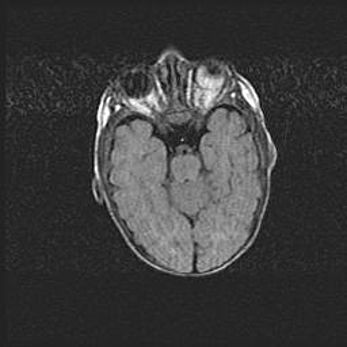

Церебральная ишемия II.

Возраст: 5 дней

Вес: 3400 г

Пол: женский

Окружность головы: 35 см

Срок гестации: 39 недель

Церебральная ишемия – это заболевание, характеризующееся недостаточностью (гипоксией) либо полным прекращением (аноксией) снабжения мозга кислородом по причине закупорки одного или нескольких сосудов. Это приводит к  что метаболическим расстройствам различной степени тяжести в тканях головного мозга, развитию коагуляционных некрозов и гибели нейронов.